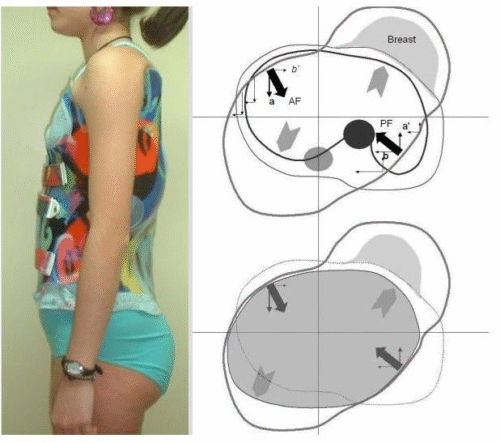

2. زيادة التقوس القطني داخل الحزام (In-brace Lordosis)

تشير الدراسات إلى أن زيادة التقوس القطني الصحي أثناء ارتداء الحزام ترتبط بنتائج أفضل.

والسبب في ذلك أن التوازن السهمي الجيد يسمح للحزام بتوزيع الضغط بشكل أكثر فعالية.

بالتالي، الحزام الذي يسمح بالحفاظ على التقوس الطبيعي للظهر يكون أكثر نجاحًا من الحزام الصلب المفرط.

3. التقوس السهمي قبل العلاج

الأطفال الذين يعانون من نقص في التقوس الطبيعي لمنطقة منتصف الظهر (Hypothoracolumbar Profile) قد يستفيدون أكثر من الحزام إذا كان لديهم تقوس قطني جيد قبل العلاج.

بمعنى آخر، شكل العمود الفقري قبل بدء العلاج يلعب دورًا مهمًا في توقع النتيجة.

5. شكل القفص الصدري

القفص الصدري ليس مجرد غطاء للرئتين، بل عنصر أساسي في تشوه الجنف.

وقد صنفت الدراسات القفص الصدري إلى نوعين رئيسيين:

قفص صدري أفقي

قفص صدري مائل أو متدلٍ

النتائج أظهرت أن الأطفال ذوي القفص الصدري الأفقي يستجيبون بشكل أفضل للحزام، خاصة إذا كان الدوران الفقري أقل.